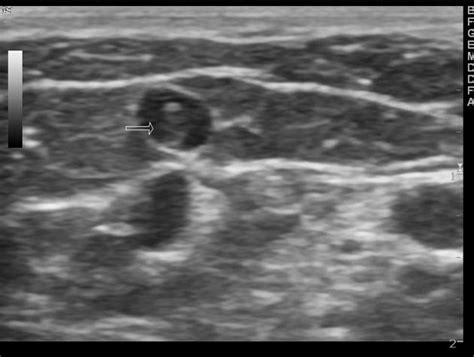

El ultrasonido dúplex es el método de elección para el diagnóstico de trombosis venosa tanto en la circulación superficial como profunda. Un trastorno menos grave que la tvp, se puede producir en los estados trombofílicos heredados y adquiridos y puede progresar a la tvp. Representa un método económico, indoloro, que no emite radiación, sin embargo, requiere de un profesional entrenado para su realización (2), Venous thromboembolism and superficial vein thrombosis account for about 90% of venous thrombosis. Venosa crónica y/o trombosis venosa profunda.

Oct 24, 2017 · portal vein thrombosis (pvt) is a blood clot that causes irregular blood flow to the liver. En un principio se puede ver que las venas varices aumentan de tamaño hasta convertirse en una especie de cordón duro al tacto. Jul 30, 2016 · la trombosis venosa superficial (tvs) o tromboblebitis es una inflamación de una vena del sistema venoso superficial debido a la presencia de un coágulo (trombo) en su interior. En un metanálisis de 21 estudios de pacientes con trombosis venosa superficial, la prevalencia de la tvp fue del 18 por ciento (di minno mn, 2016). 1 es una forma de trombosis venosa que usualmente afecta las venas en la parte inferior de la pierna y el muslo, como la vena femoral o la vena poplítea, o las venas profundas de la pelvis. Some of these can also lead to pulmonary embolism. Etiologia existen varios factores de riesgo bien reconocidos que actúan para La trombosis venosa profunda —generalmente abreviada como tvp— consiste en la formación de un coágulo sanguíneo o trombo en una vena profunda. Representa un método económico, indoloro, que no emite radiación, sin embargo, requiere de un profesional entrenado para su realización (2), Venous thromboembolism and superficial vein thrombosis account for about 90% of venous thrombosis. El ultrasonido dúplex es el método de elección para el diagnóstico de trombosis venosa tanto en la circulación superficial como profunda. Su color es azulado y pueden causar dolor intenso. Estasis venoso (varices, inmovilización, obesidad), embarazo, anticonceptivos orales, neoplasia, trombofilias hereditarias, e inyección intravenosa de sustancias irritantes (fármacos, estupefacientes) (mermel la.